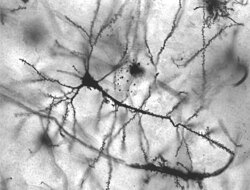

Ona vodi porijeklo od interne medicine. Krajem 19. stoljeća osnovana je na Medicinskom fakultetu u Parizu prva katedra za neurologiju. Posebno se bavi opisom i objašnjenjem kliničke slike bolesti prouzrokovane patološkim procesima i lezijama u određenim strukturama živčanoga sustva ili poremećajima u njegovom funkcioniranju. Neurologija i psihijatrija se dijelom isprepliću. Predmet proučavanja neurologa su: središnji živčani sustav, (mozak i leđna moždina), kao i njima bliske strukture krvnih žila, perifernih živaca i veza živaca s muskulaturom.